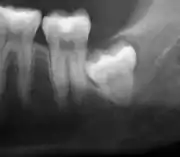

Impacted wisdom tooth with no tilt (vertical impaction)

Impacted wisdom tooth that is tilted forward (mesioangular impaction)

Impacted wisdom tooth with a horizontal orientation (horizontal impaction)